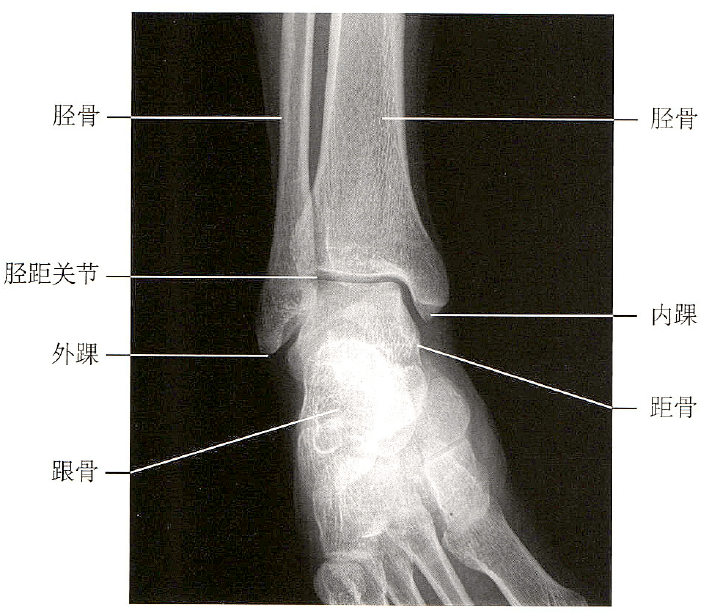

踝关节正侧位

踝关节侧位x线

足踝关节解剖丨骨骼,关节,软组织_韧带_白箭_显示